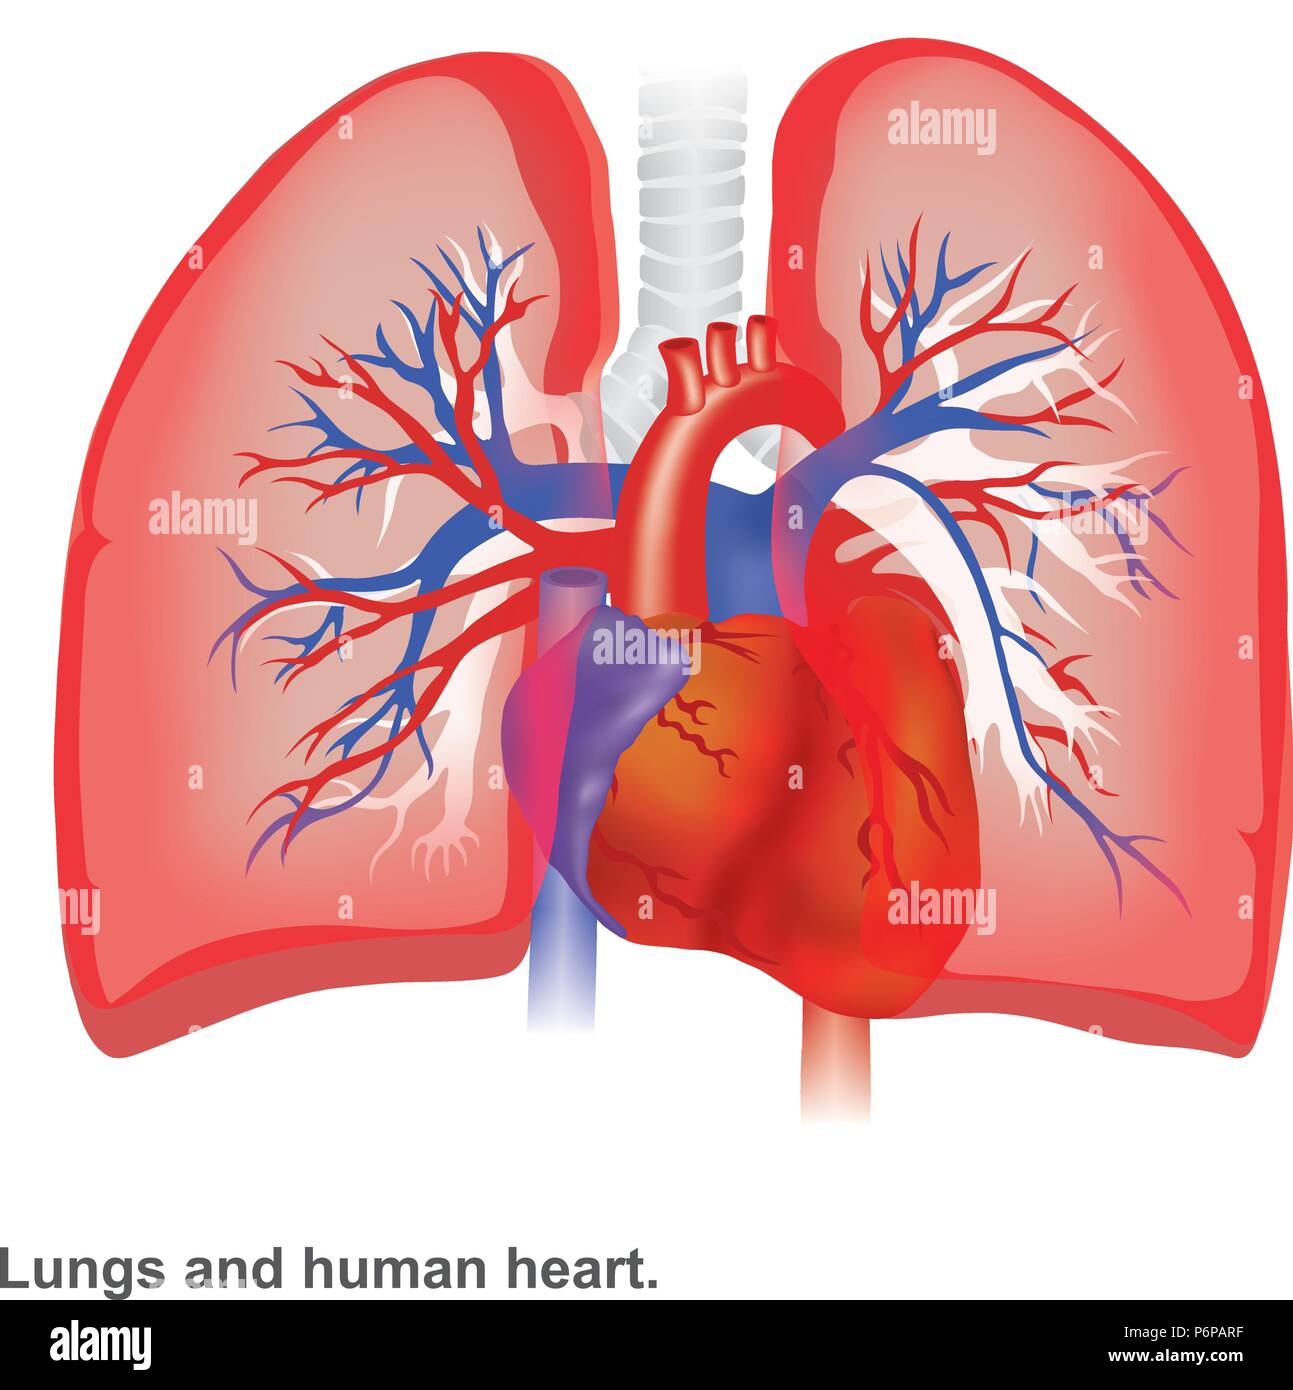

I polmoni e il cuore umano illustrazione anatomia infografico. Illustrazione Vettorialehttps://www.alamy.it/image-license-details/?v=1https://www.alamy.it/i-polmoni-e-il-cuore-umano-illustrazione-anatomia-infografico-image210703795.html

I polmoni e il cuore umano illustrazione anatomia infografico. Illustrazione Vettorialehttps://www.alamy.it/image-license-details/?v=1https://www.alamy.it/i-polmoni-e-il-cuore-umano-illustrazione-anatomia-infografico-image210703795.htmlRFP6PARF–I polmoni e il cuore umano illustrazione anatomia infografico.